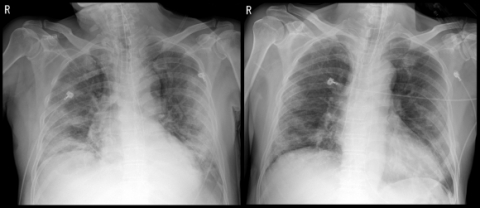

미국 식품의약국(FDA)이 신종 코로나바이러스 감염증(코로나19) 혈장치료제의 긴급사용을 승인했다. 24일 연합뉴스에 따르면 FDA는 오늘 성명을 통해 코로나19 혈장치료제를 입원 후 사흘 안에 처방받은 환자들의 사망률이 감소하고 상태가 호전됐다고 밝혔다. FDA는 코로나19 진단을 받고 입원한 뒤 3일 이내에 혈장치료를 한 환자들의 상태가 호전됐고, 사망률 역시 감소한 것으로 나타났다고 전했다. 혈장치료는 코로나19 완치자의 혈장 안에 들